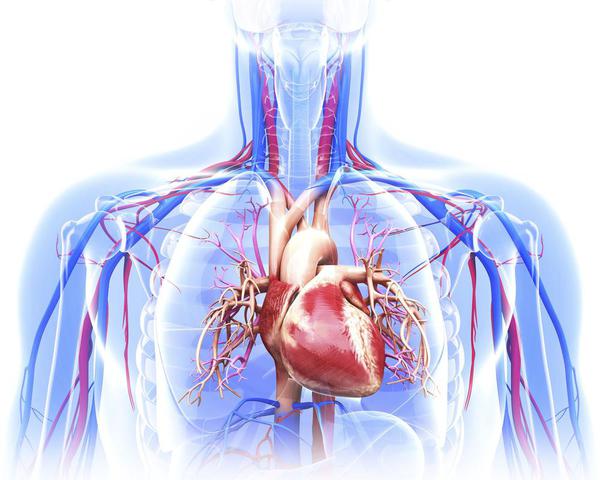

The Heart: Anatomy, Function, and Conditions

The heart—the primary organ of the cardiovascular system—is a muscle that contracts regularly, via a natural pacemaker that produces electrical impulses. The heartbeat drives the transport of blood throughout the body, which provides oxygen and nutrients to all the body’s cells, tissues, and organs. Although the heart is a complicated organ, in essence, it is a pump that continuously works to circulate blood throughout the body.

The heart is an organ that weighs approximately 350 grams (less th